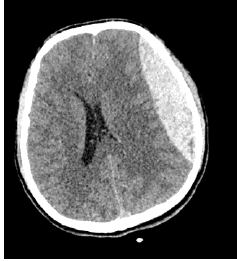

Paciente, sexo masculino, 23 anos, admitido em pronto-socorro do hospital de sua cidade após sofrer acidente automobilístico há cerca de 40 minutos. Segundo testemunhas do local, o paciente ficou desacordado por alguns minutos e, desde o momento que acordou, queixa-se de dor de cabeça intensa e constante. Realizada tomografia computadorizada de crânio que evidenciou o seguinte resultado:

Qual o achado da tomografia de crânio realizada?